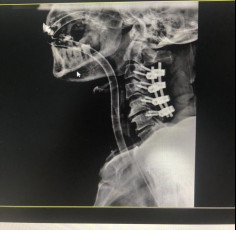

(術后拍片)

治療效果顯著康復出院

今年5月,張阿伯出院近2月后,大部分生活已經可以自理。戈主任為張阿伯做了復查診治,結果顯示他的頸椎固定可靠,復位良好,病體正在朝理想的康復方向發(fā)展。